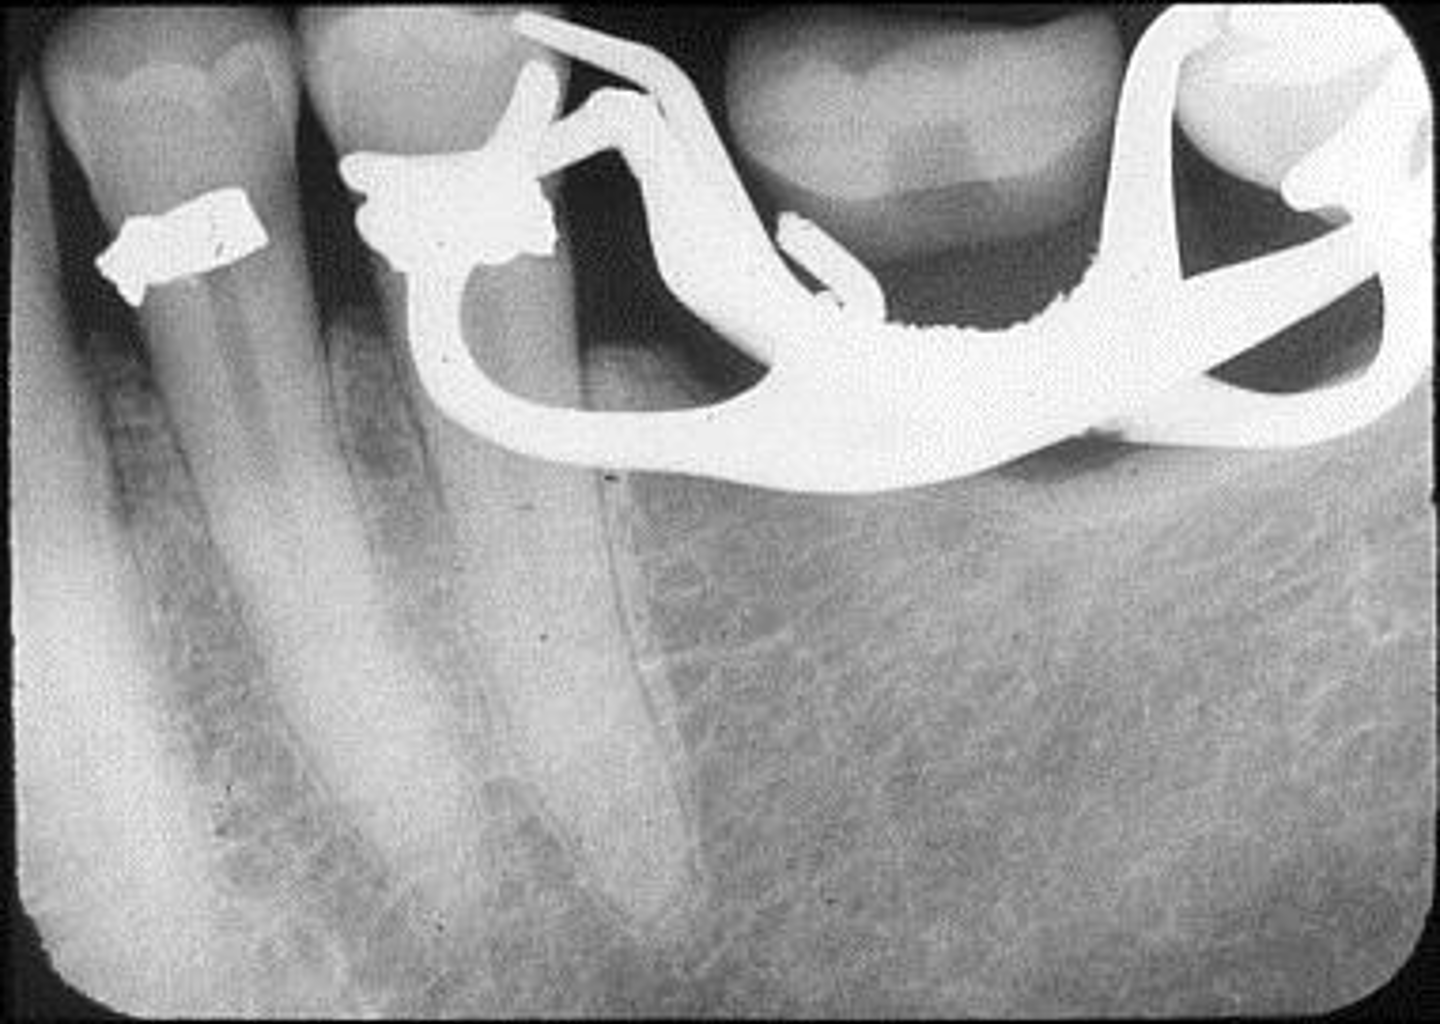

Wrong film direction, backwards, positive angulation, wrong film size, no open contacts

What is this error?